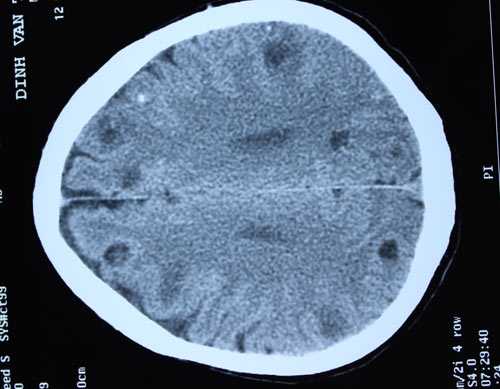

| Ổ sán trong não bệnh nhân. |

Không nằm ngoài dự đoán kết quả chụp CT sọ não của bệnh nhân cho thấy rất nhiều sán trong não. Nhìn kết quả chụp các bác sĩ cũng phải tá hóa bởi mỗi lát cắt chụp não phát hiện 4-5 ổ sán não, tính chung trong não của bệnh nhân có tới trên dưới 50 ổ sán làm tổ.